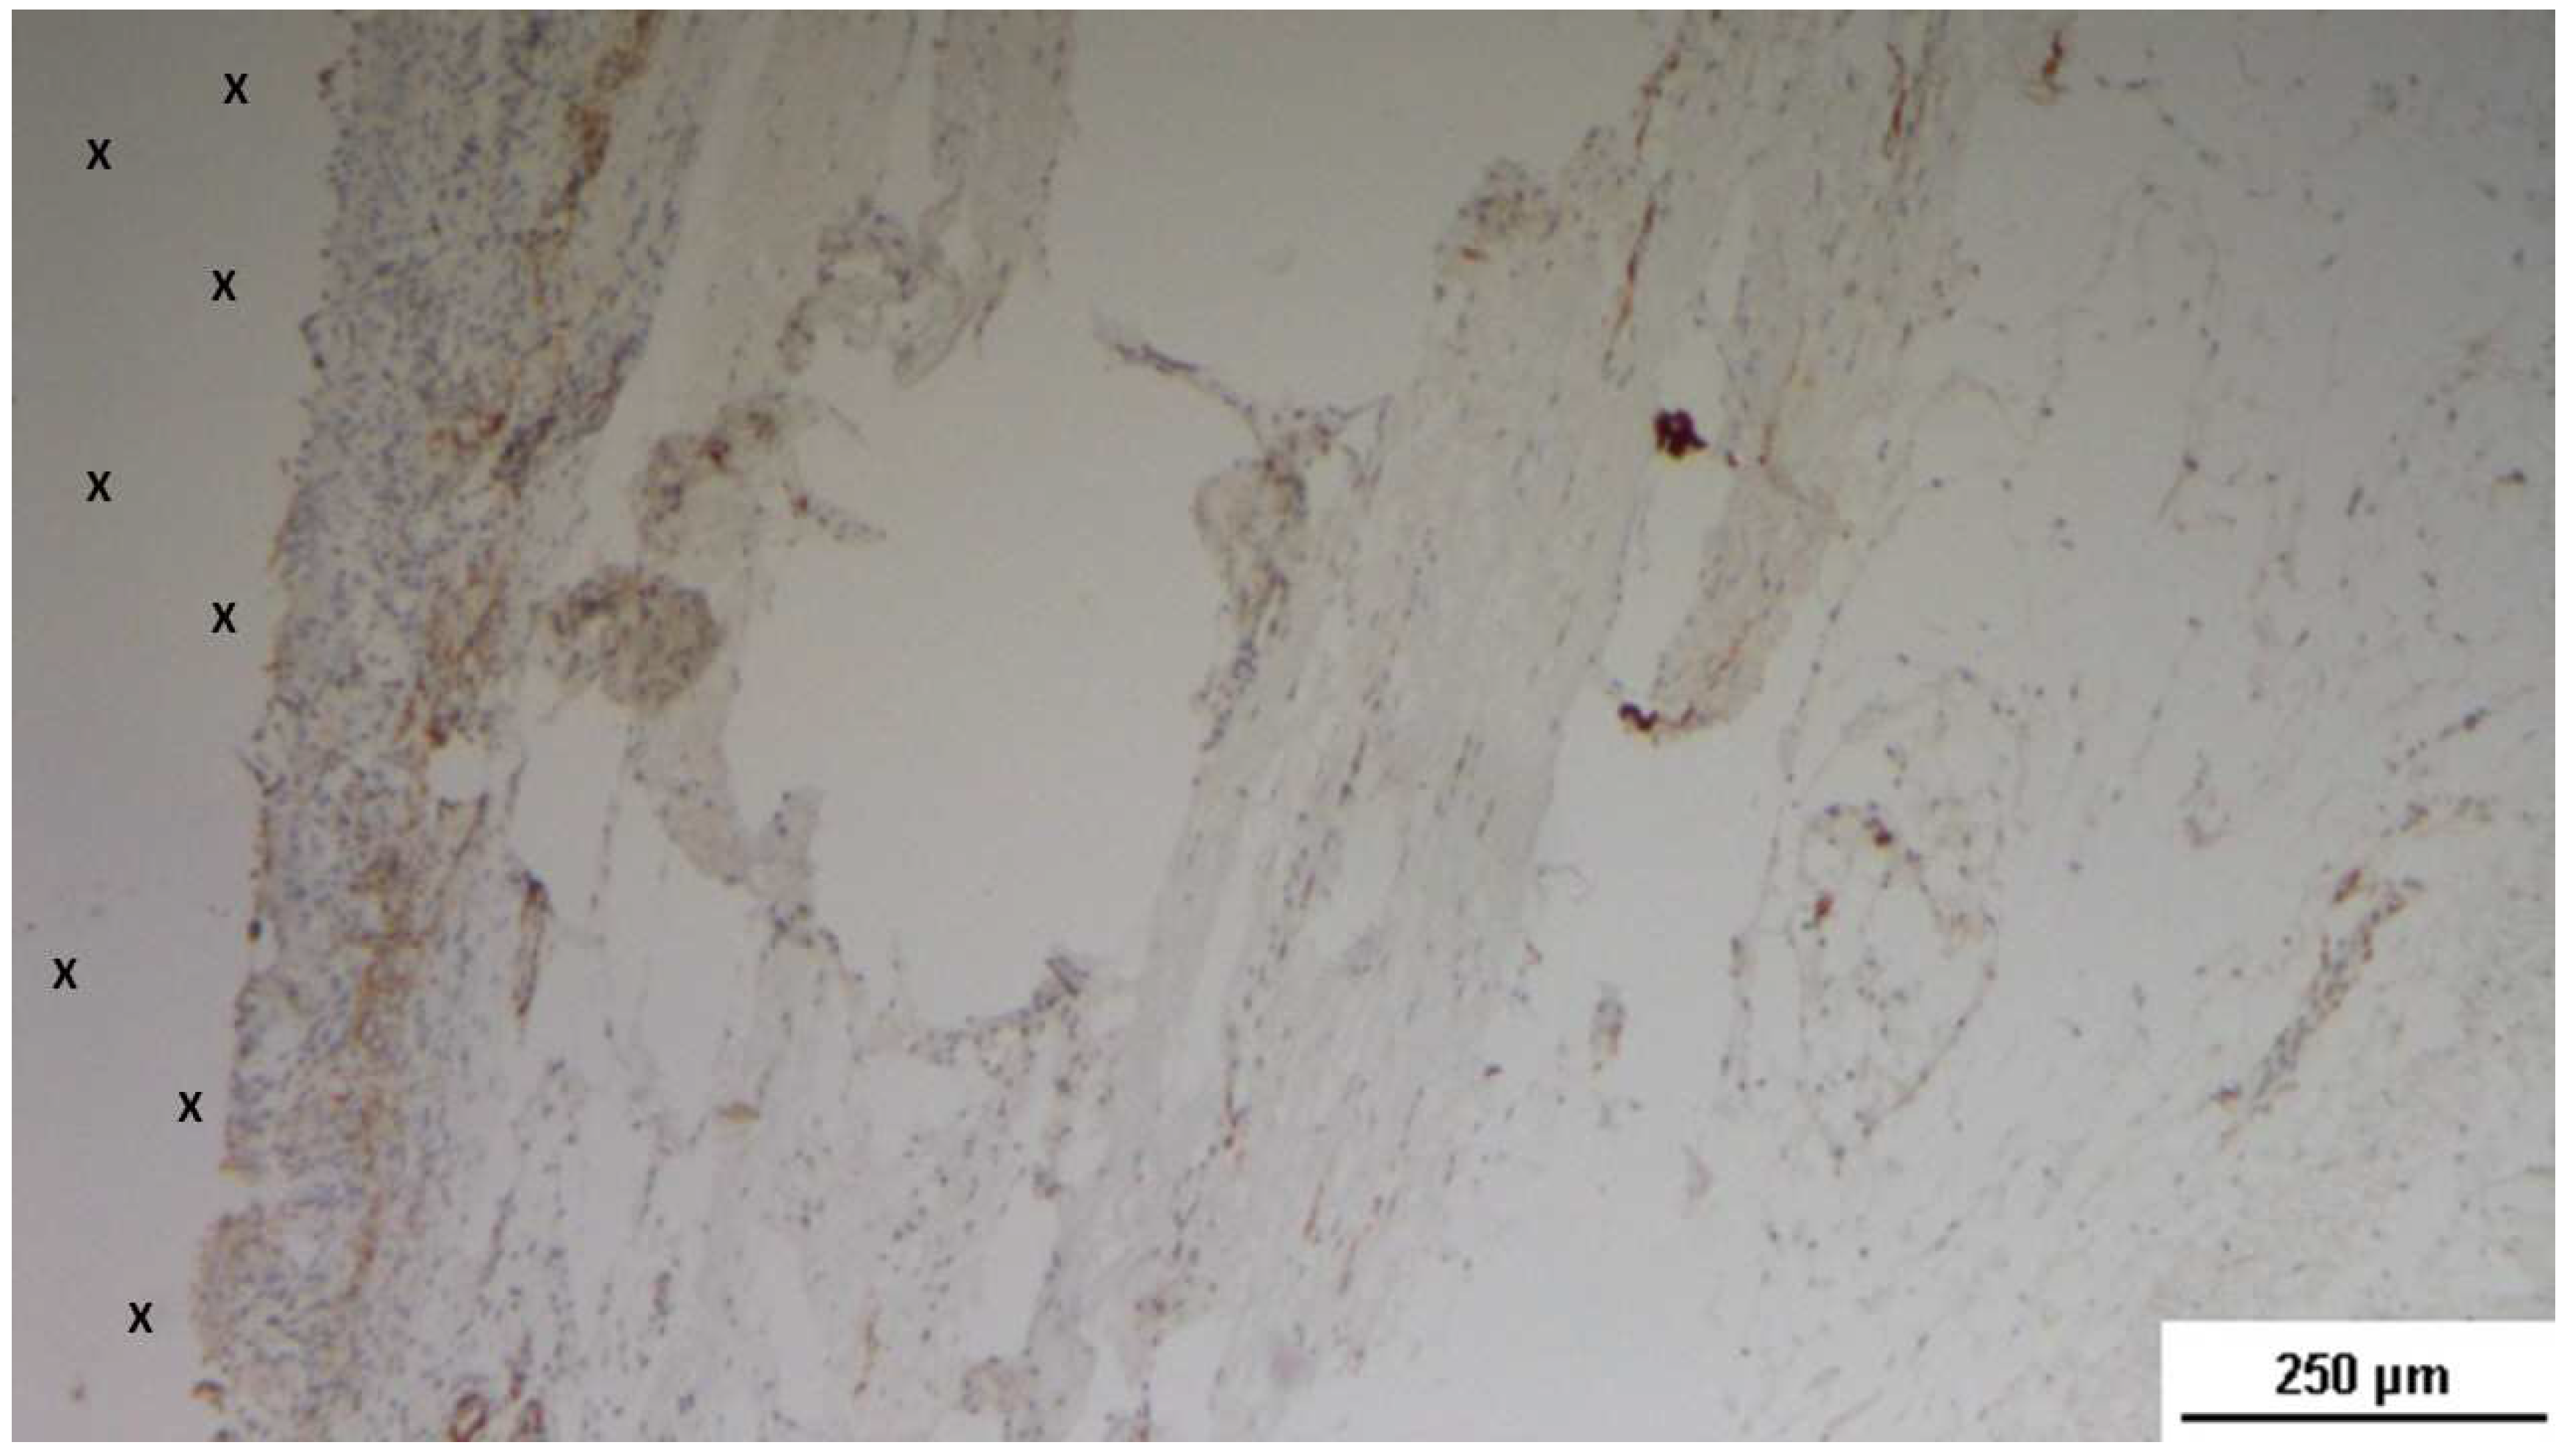

Figure 26. Biopsy sample removed 7 months post-implantation (Long term - LT). Elongated nerve elements (brown staining) in advanced development are present near the 3D scaffold (X). NSE 100X.